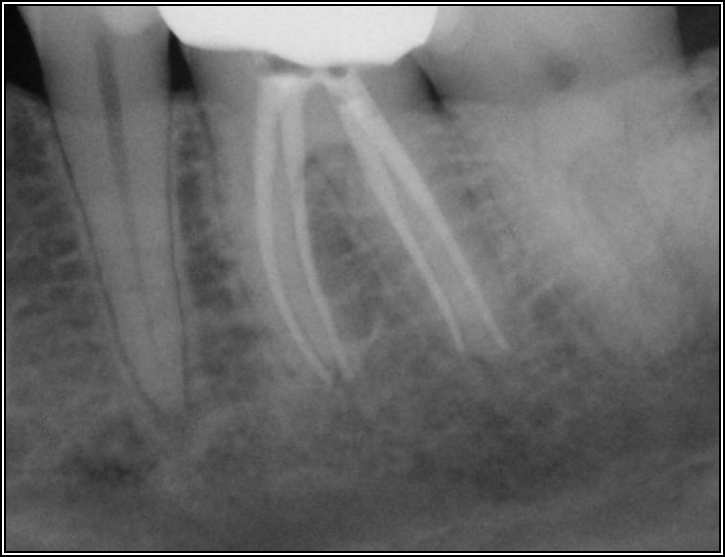

If a tooth stands alone, greater forces will be placed on it because it has no adjacent teeth to provide support. This situation will affect the decision-making process for placing a post. Figure 3 shows a tooth that was on an island and would be having three implants placed in front of it. The tooth would take a much greater beating than another tooth that had support proximally. Even though it had a good root canal, the clinician would need to account for whether the tooth would last until the implants integrated. Figure 4 shows a case that would quickly proceed to implants. The patient had a less-than-ideal bridge for over a decade, with decent endodontics and functionality. There was also an overhang on the premolar. The post was not ideal in this case because there was one distal canal and not all the gutta-percha was removed from it. An intimate fit should be the goal with the post and the walls. Whether using a threaded or non-threaded post, there should not be excess gutta-percha because it is not as solid as the tooth and will lead to greater movement. That movement on the tooth and bridge will create too much force and result in demise.

Fig 3. Tooth on an island.

Figure 3

Fig 4. Case that quickly would proceed to implants.

Figure 4